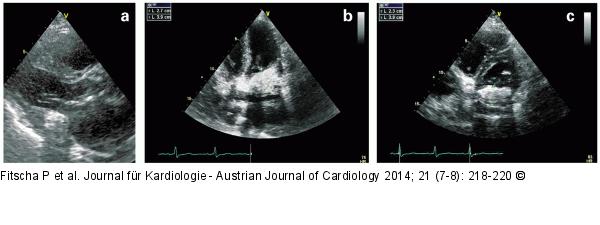

Abbildung 3a-c: Hyperdense echogene Struktur Hyperdense echogene Struktur im Bereich des posterioren Mitralrings: (a) Parasternaler Längsschnitt, (b) Vierkammerblick, (c) parasternaler Querschnitt |

Hyperdense echogene Struktur im Bereich des posterioren Mitralrings: (a) Parasternaler Längsschnitt, (b) Vierkammerblick, (c) parasternaler Querschnitt |